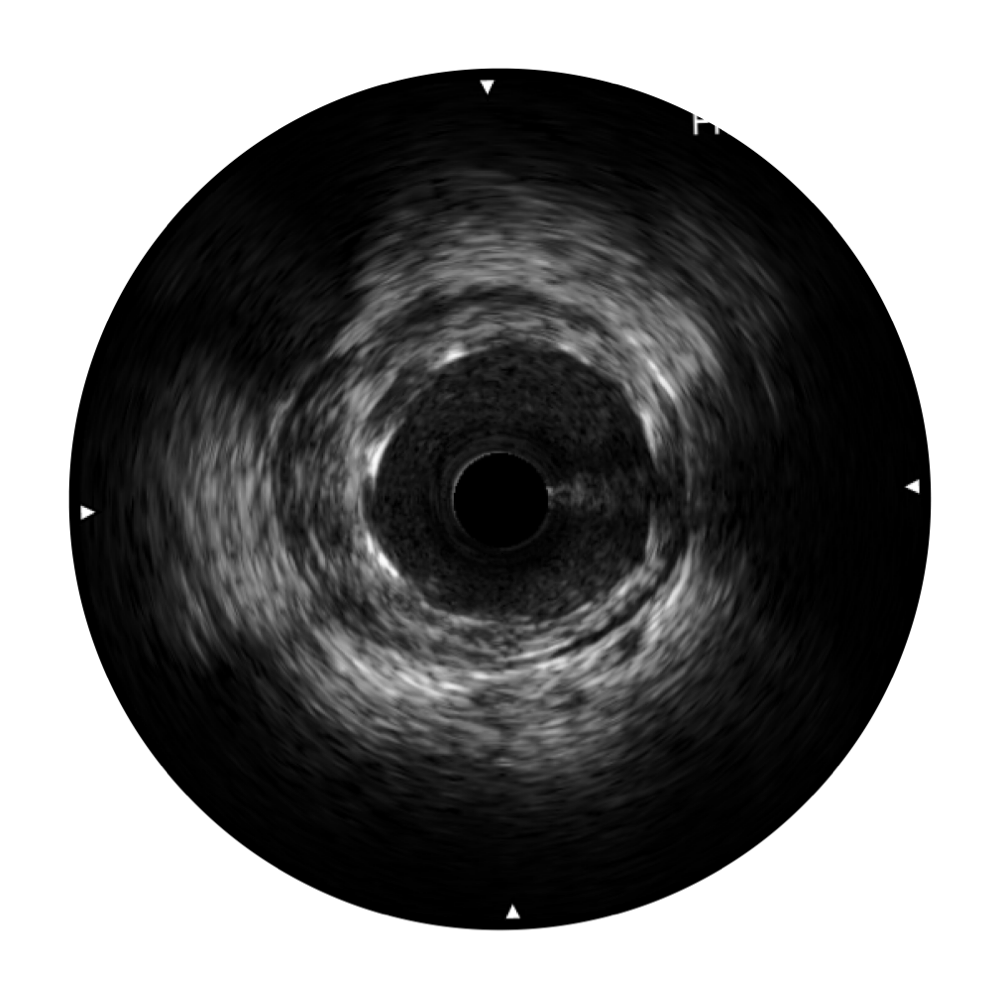

血管内超声(IVUS) 通过对病变程度、性质和累及范围的精确判断,可帮助选择治疗策略和方法,指导介入治疗过程,能够降低主要不良心血管事件,改善预后,在复杂病变介入治疗中用于指导支架置入的优势更为明显。血管内超声(IVUS)已成为精准心血管介入治疗的“金标准”。

1xBET超宽频成像技术覆盖20-80MHz1或20-90MHz2频率范围, 提供优异的分辨力同时也保证充足的穿透深度